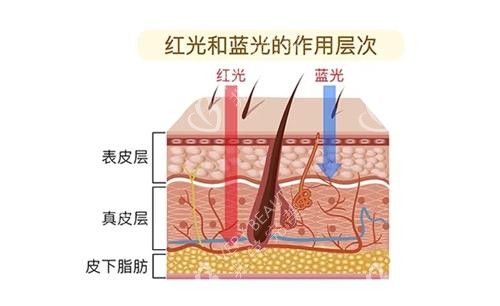

四、红蓝光:单次300-800元,痤疮治疗性价比高

红蓝光通过不同波长光波杀菌,适用于痤疮、炎症修复。

价格差异原因:设备类型(如进口vs国产)、治疗面积(如局部vs全脸)、附加服务(如是否包含药物配合)均会影响定价。部分机构推出“痤疮套餐”(红蓝光+针清+药物),总价约800-1200元。